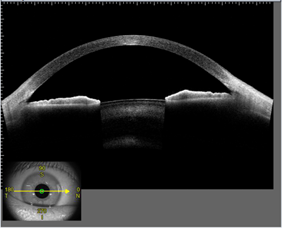

角膜混濁、円錐角膜などの角膜疾患や狭隅角眼などの術前/術後の検査に威力を発揮します。

また角膜厚や隅角角度などの各種定量解析も正確に行えます。